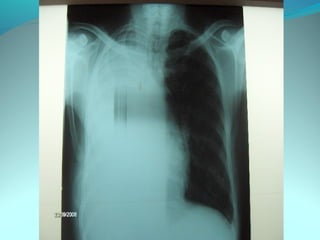

2 hyper clarté avasculaire occupant la quasi-totalité de l HT G

séparées par du parenchyme pulmonaire qui reste attache au sommet

par une opacité correspondant une bride

La hydrique est périohérique allant de sommet a la base de 5cm

d’épaisseur a sa partie inf et de 3cm a l supr; la limite supero ext se

confond a la paroi; la limite interne correspond au poumon

Pa de signe de distension ni de refoulement

DIAGNOSITC:

PNO gauche bride